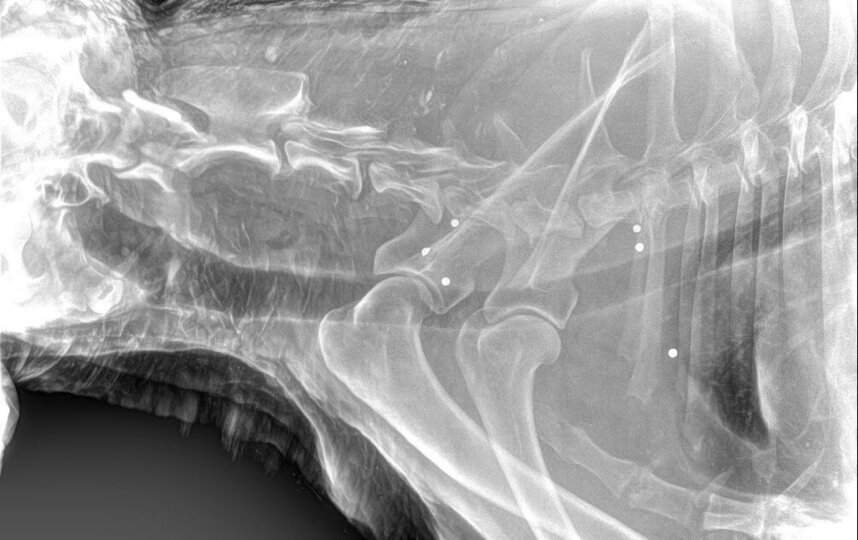

Специалисты привезли животное в ветеринарную клинику, где на рентгене стали видны многочисленные огнестрельные ранения. Из тела пса достали пули разной степени давности, сообщает телеграм-канал Mash на Мойке.

Кто ранил пса и кто был его хозяином – пока не выяснили. По оценкам ветеринаров, состояние животного – средней степени тяжести. Псу дали имя Миша, ему примерно десять лет. После окончания курса лечения животному найдут новых ответственных владельцев.